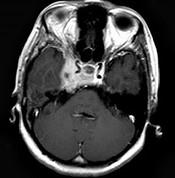

问题 女,34岁。右侧听力下降,耳鸣2个月。MRI平扫及增强扫描如图示,最可能的诊断是()

选项 A.鼻咽癌 B.脑膜瘤 C.神经源性肿瘤 D.动脉瘤 E.未见异常

答案 A